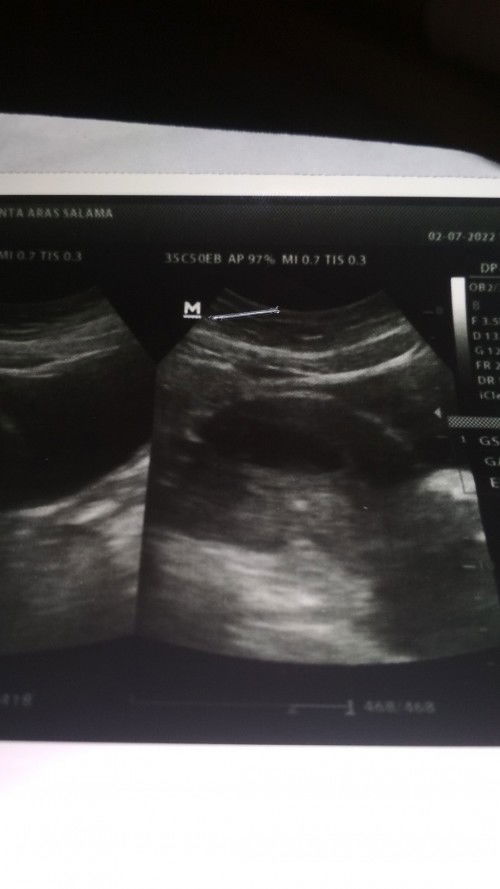

Pendarahan seperti haid padahal sudah meminum penguat kandungan di usia kandungan 8 w 4d

#bantusharing apakah foto usg ini hamil kosong

@Herlin Mamax'Dirga sebisa mungkin bedrest total ya bun jgn ada aktivitas sama sekali mencegah yg tdk diinginkan n kl bisa perut jgn ada goncangan sama sekali mudah2an USG berikutnya sudah terlihat janinnya